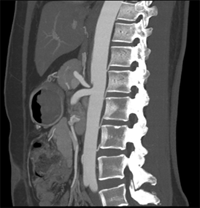

如上圖所示,相鄰的三張軸位圖像未見明顯異常,根據(jù)傳統(tǒng)軸位圖像很難得到準確的臨床診斷。

同一病人利用容積數(shù)據(jù)進行三維處理后,高品質(zhì)MPR和三維圖像上則清晰顯示了縱向排列的腹腔干與腸系膜上動脈相鄰近,血管發(fā)生變 異,近端血管閉塞,為臨床提供了精確的診斷信息。